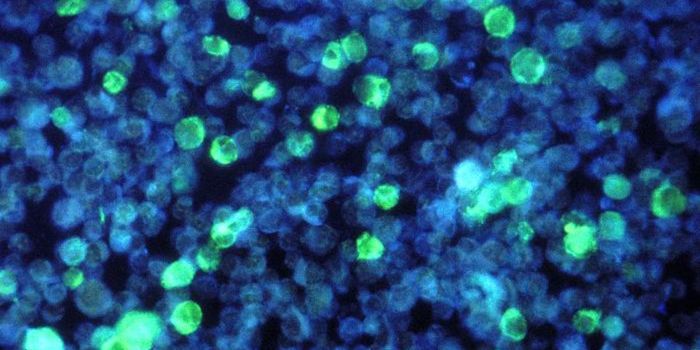

JUL 19, 2016CancerA decade-old technology to arm the immune system to fight cancer is now being adapted to fight HIV, one of the most pern ...

DEC 10, 2016ImmunologyFor high-risk cancer patients with acute myeloid leukemia (AML), oncologists are interested in supplementing bone marrow ...

JAN 27, 2017Cell & Molecular BiologySeveral years after receiving the treatment, scientists have confirmed that two infants with cancer that received a type ...

JUN 24, 2017CancerOur immune system has an extraordinary capacity to fight pathogens and protect the body. Indeed, some immune cells can f ...